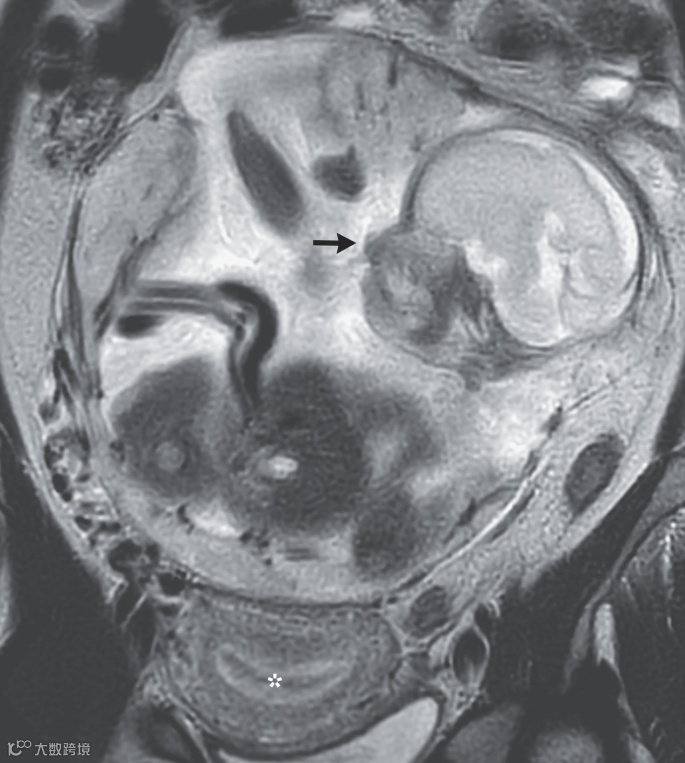

透過磁力共振掃描(MRI),醫生清楚地看到了完整的人類胎兒影像,同時發現孕婦的子宮相對空虛。這項發現讓許多人感到不可思議,尤其是在這樣一個發達的醫療時代,居然會出現如此罕見的子宮外孕案例。(下面打星號處)

在孕婦懷孕29週時,醫師決定進行剖腹產,成功取出了胎兒及胎盤。經過兩個月的住院觀察和照顧,母嬰兩人的健康狀況良好,胎兒最終得以出院。